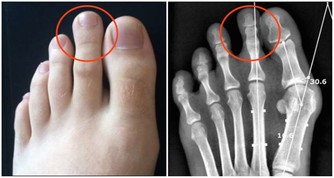

血液中的「血垢」是指膽固醇、甘油三酯等,它們在血管壁上越積越多,形成如同黃色小米粥樣的斑塊。